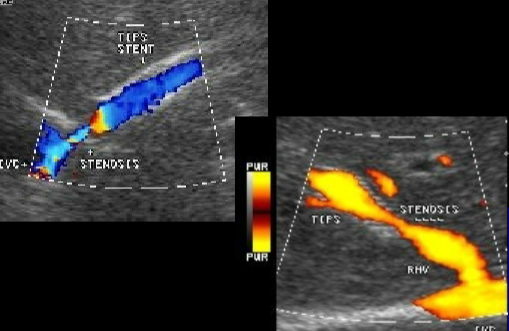

TIPS